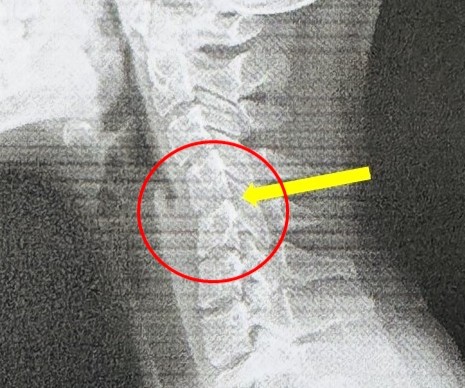

An X-ray revealed a shocking truth – her cervical spine had lost its natural inward curve and, in some areas, vertebrae showed signs of slippage.

Her condition, commonly known as “text neck”, is an early warning of premature cervical degeneration.

Misaligned cervical vertebrae caused by text neck can also affect blood flow to the brain, triggering chronic headaches and dizziness.

It can even accelerate disc herniation and bone spur formation, bringing skeletal problems typically seen in older adults decades earlier.